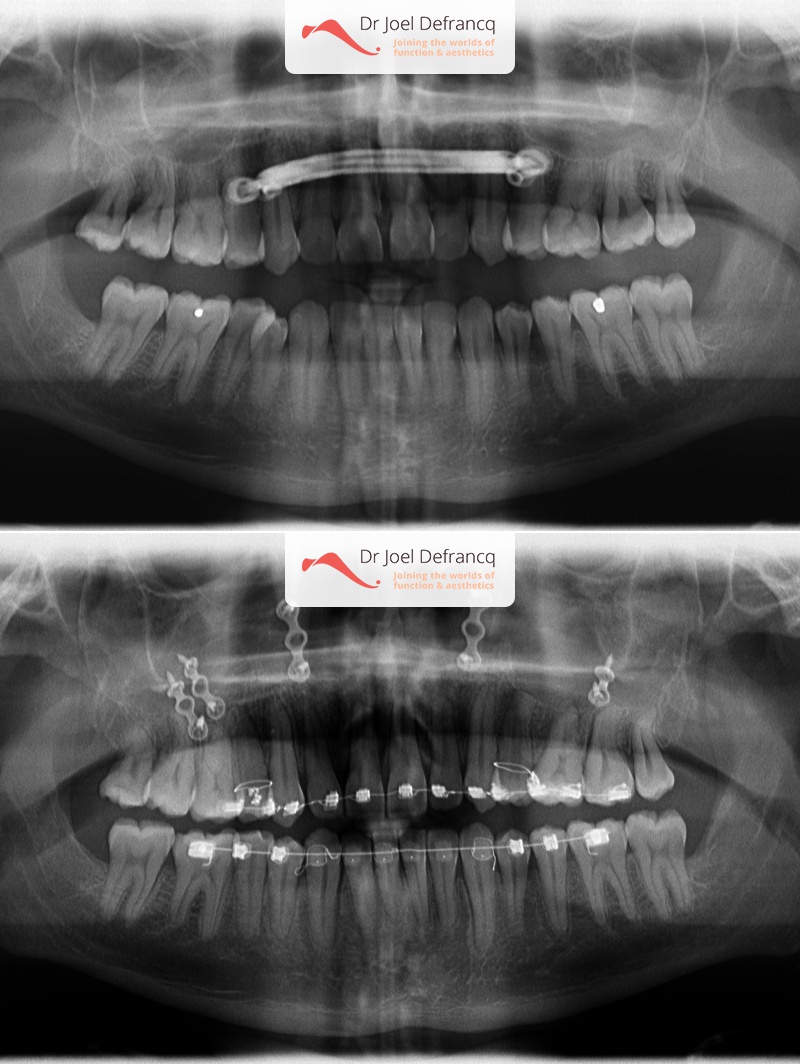

Natan: Kaakchirurgie voor en na. Te nauwe bovenkaak

Diagnose van het gezicht

- Te kleine bovenkaak

Dentale diagnose

- Klasse III

- Randbeet

Kaakchirurgie

- Verlenging bovenkaak (Le Fort I)

- Verbreden bovenkaak (Smile distractor)